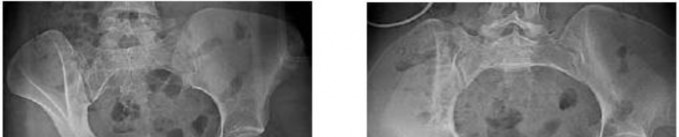

Q. 1Figure 1 is the radiograph of a 62-year-old woman who fell and sustained a left hip fracture. A radiographis shown in Figure 1. Which of the following preoperative risk factors is associated with the highest postoperative mortality rate?

Figure 7Figure 7 is the pelvic radiograph of a 33-year-old man involved in a high-speed automobile crash. Examination reveals a blood pressure of 90/50 mm Hg and a pulse rate of 120/min. Radiographs of the chest and lateral cervical spine are normal. A CT scan of the abdomen does not reveal any intraabdominal bleeding. What is the most appropriate management for the pelvic fracture?